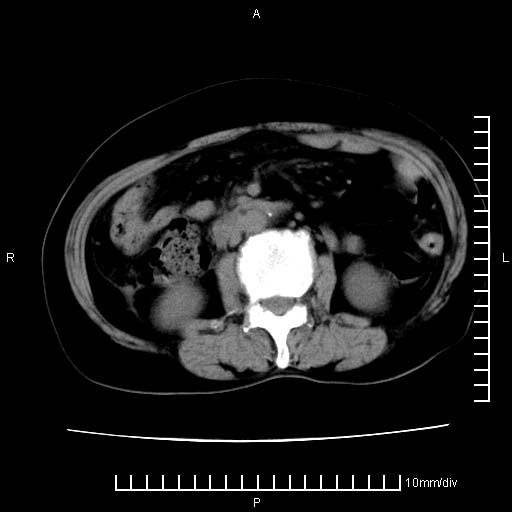

下腹疼痛2月,加重并呕吐2天,下腹压痛,反跳痛。白细胞1万2.

下腹至盆腔较大包块,与邻近肠管关系密切,下腹疼痛2月,加重并呕吐2天,下腹压痛,反跳痛。白细胞1万2.

由于没有做肠道准备很难分清是哪根肠管,但看位置考虑为升结肠回盲部的问题,我首先考虑化脓性阑尾炎,不除外结肠癌合并感染化脓。建议做增强进一步明确。

补充:道格拉斯腔内有积液,且密度较高,显然提示有感染。